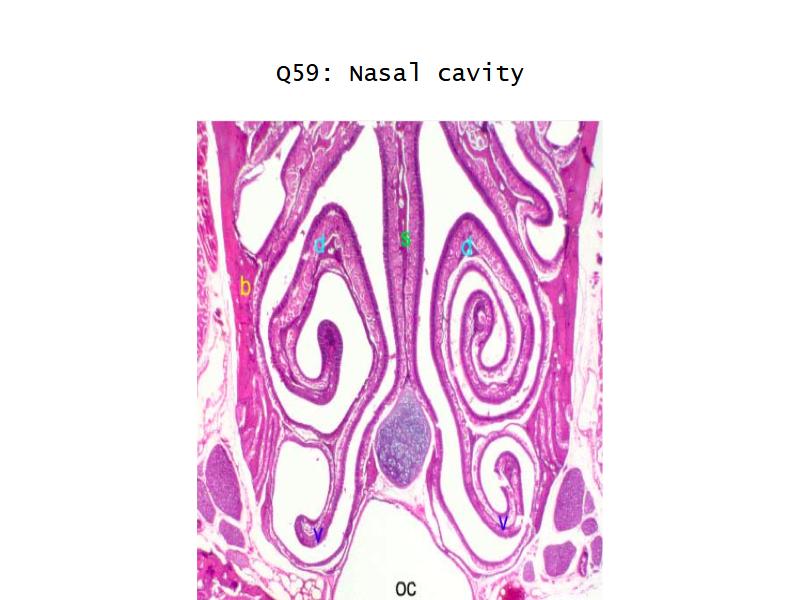

Function of the nasal cavity?

Function of the nasal cavity?

- Warm

- Moisture

- Filter

- Smell